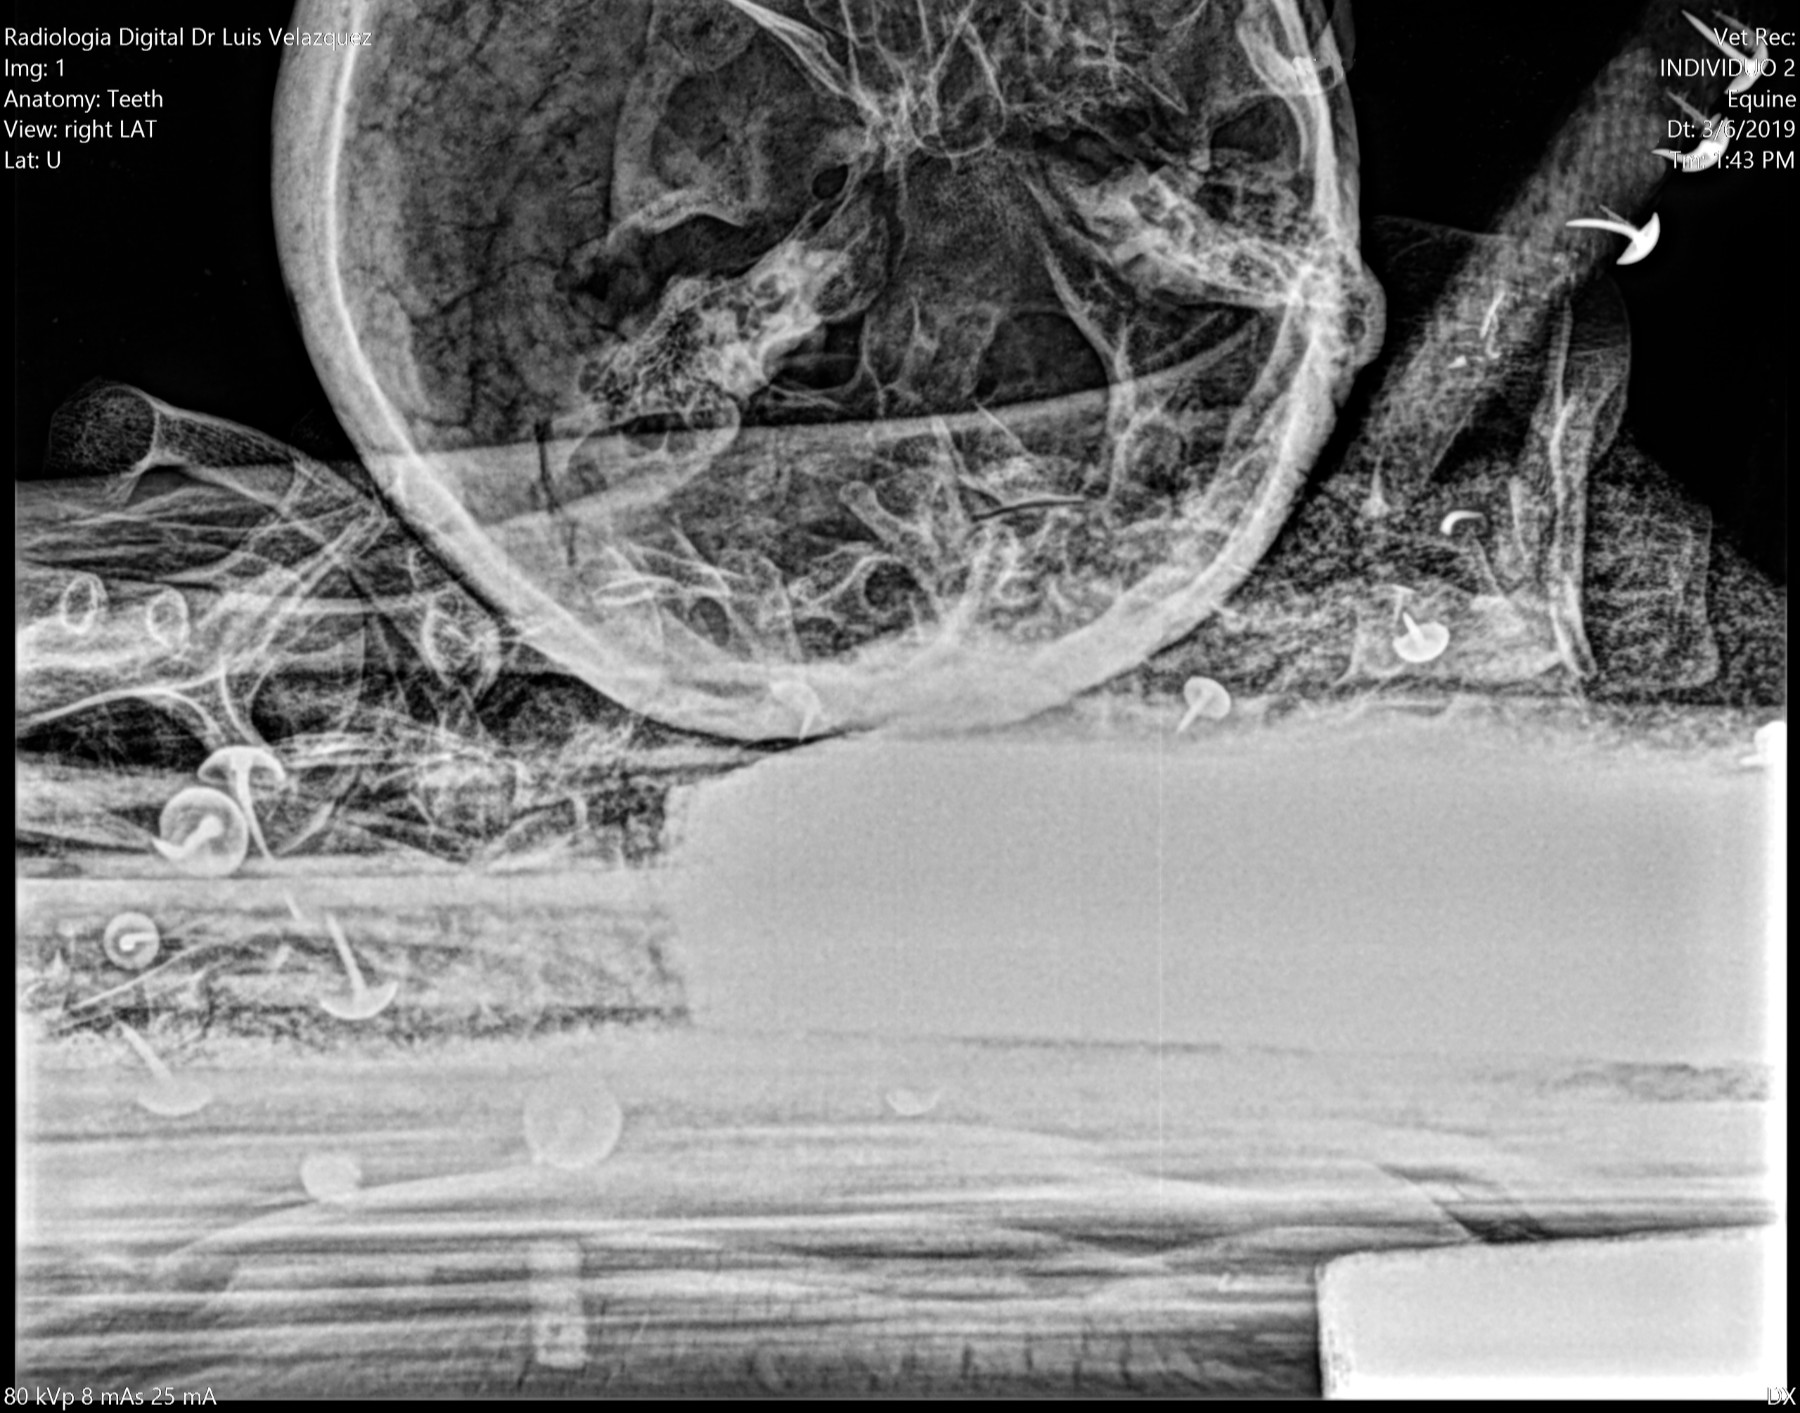

THE GENUS RHYNCHOTERIUM (MAMMALIA-PROBOSCIDEA) in the Hemphilliam - Blancan (NALMA) of central Mexico

In research in Neogene deposits from central Mexico, have collected abundant fossil materials, that have been referred to Rhynchotherium, based in not diagnostic materials and inaccurate age and locality, that not adequately di erentiate between the genus Rhynchotherium, Cuvieronius and Gomphotherium (Lucas y Morgan 2008).